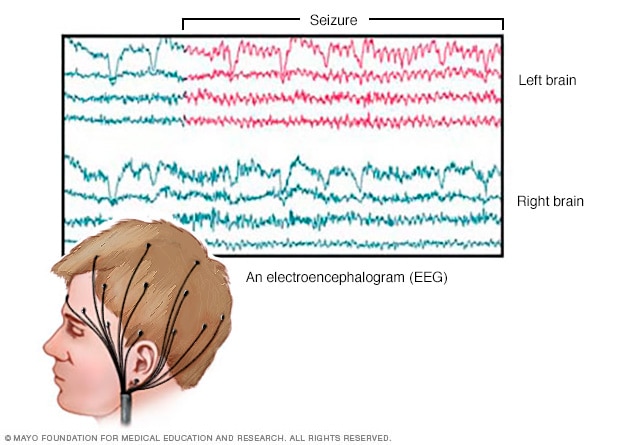

EEG brain activity

An EEG records the electrical activity of the brain through electrodes put on the scalp. EEG results show changes in brain activity. This may help diagnose brain conditions such as epilepsy and other seizure conditions.

Electroencephalogram (EEG). This is the most common test used to diagnose epilepsy. In this test, small metal discs called electrodes are attached to your scalp with an adhesive or cap. The electrodes record the electrical activity of your brain.

If you have epilepsy, it's common to have changes in the pattern of brain waves. These changes occur even when you're not having a seizure. Your healthcare professional may monitor you on video during an EEG to detect and record any seizures. This may be done while you're awake or asleep. Recording the seizures may help determine what kind of seizures you're having or rule out other conditions.

The test may be done in a healthcare professional's office or the hospital. Or you may have an ambulatory EEG. The EEG records seizure activity over the course of a few days at home.

You may get instructions to do something that can cause seizures, such as getting little sleep prior to the test.

- High-density EEG. In a variation of an EEG test, you may have a high-density EEG. For this test, electrodes are placed closer together compared with a conventional EEG. High-density EEG may help more precisely determine which areas of your brain are affected by seizures.